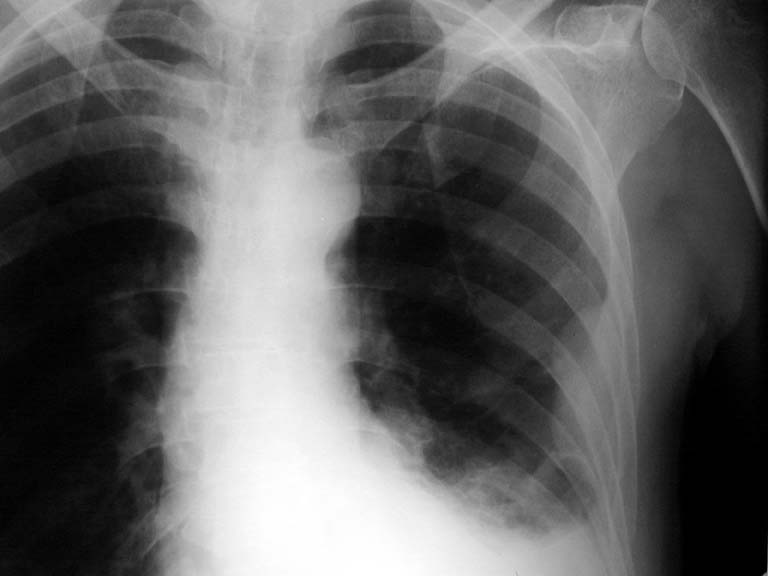

Pleural Effusion

• Homogenous density

• Loss of cardiophrenic angle

• Loss of diaphragmatic and apex of heart silhouette